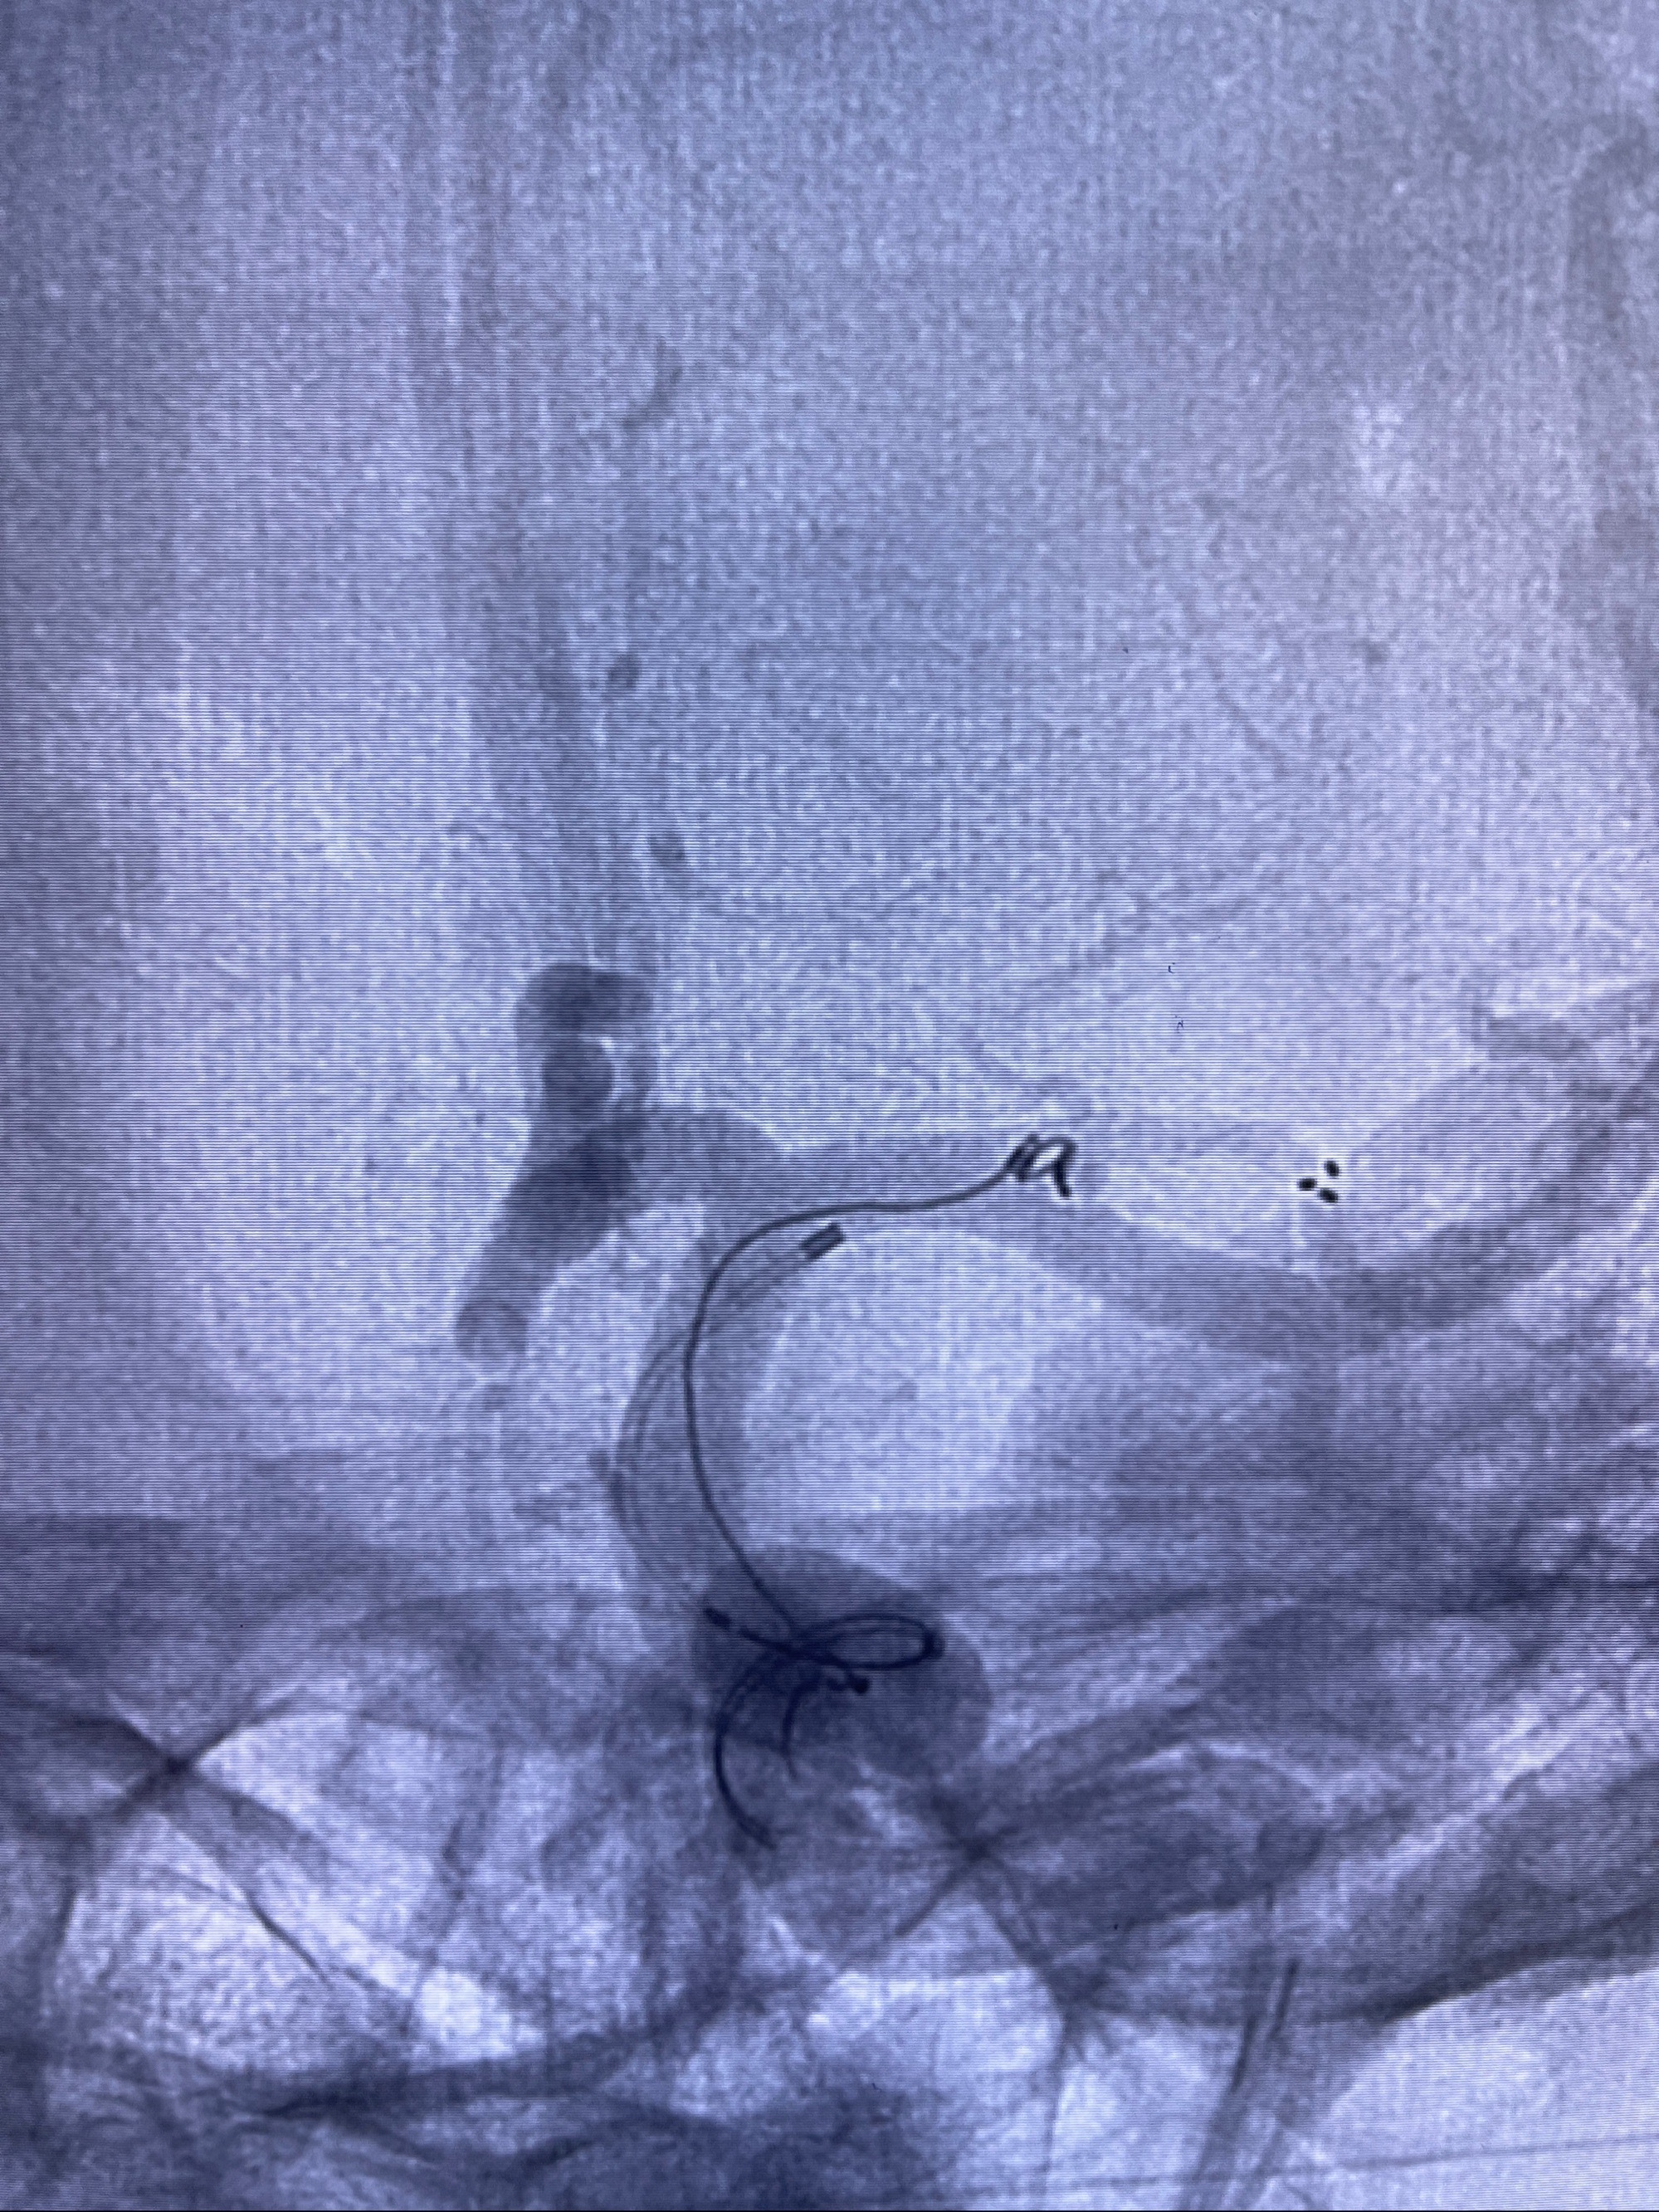

2023-08-14DSA:

左侧大脑中动脉动脉瘤,约2.6-2.8-3.4-2mm大小(瘤颈部、瘤体部、瘤高)

1.左侧大脑中动脉动脉瘤,约2.6-2.8-3.4-2mm大小(瘤颈部、瘤体部、瘤高)

2.外科手术夹闭or介入支架辅助栓塞